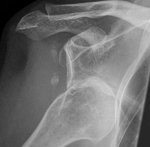

I was lying in bed, just revelling in

bank holiday languor when you

walked in and said ‘can you

take me to hospital, babe.

I’ve broke me shoulder’